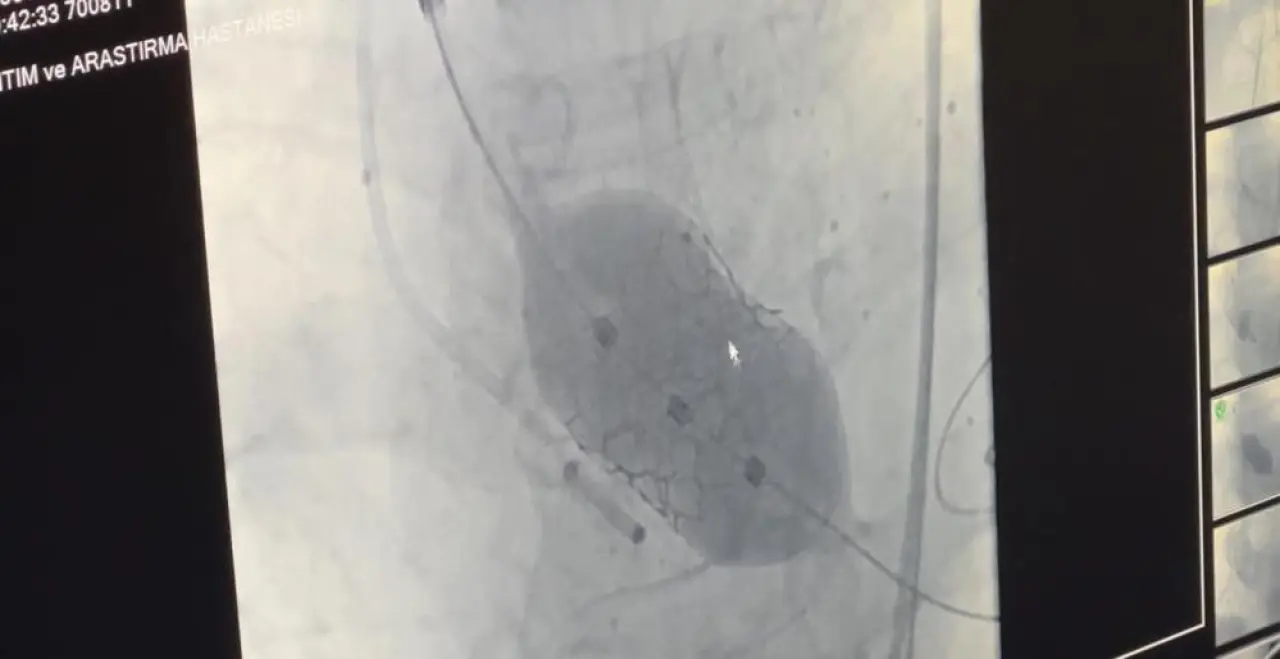

Operasyonu gerçekleştiren Samsun Üniversitesi Tıp Fakültesi Kardiyoloji Ana Bilim Dalı Öğretim Üyesi Doç. Dr. Mustafa Yenerçağ, “Hastamızda yaptığımız değerlendirmelerde, toplumda 100 bin kişide yalnızca 4 kişide görülen ‘quadricuspid’ yani dört yaprakçıklı aort kapağı tespit ettik. Literatür taramalarımızda bu tür kapağa TAVİ işlemi yapılan sadece 17 vaka bulabildik. Türkiye’den ise böyle bir vaka kaydına rastlayamadık,” dedi.

Yenerçağ, hastanın yaşı ve açık kalp ameliyatının taşıdığı yüksek risk nedeniyle TAVİ yöntemini tercih ettiklerini belirterek, “Açık ameliyat yerine kateter yardımıyla yapılan kapalı yöntemle başarı sağladık,” dedi.